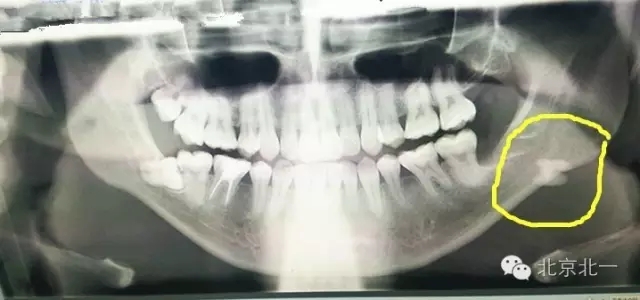

圖一:手術(shù)前(哈爾濱同行提供,接收外院患者,單位不詳)X片可見下頜骨中央高密度影像。

640.webp.jpg